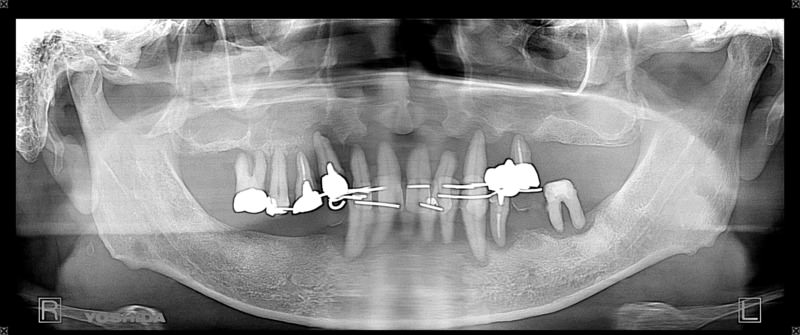

症例560代 男性 主訴 全体的に歯がグラグラしていて、しっかり噛めない

治療前

治療後(6年経過)

※説明

主訴 全ての残存歯がホープレス状態である為、インプラントを希望。抜歯前に即時義歯の総義歯を作製。ずれてしまっている顎関節の位置を補正・咀嚼のリハビリ・嚥下機能の回復を促した。その後、本来あるべきポジションにインプラント埋入を開始した。上下共に6本ずつ、計12本のインプラントを埋入。

上顎左右臼歯部の4本は、骨の高さが不足していた為、ソケットリフト(骨造成)を採用。免荷期間を経て、ケラターアタッチメントを用いたオーバーデンチャーを装着。人工歯のメタルアップにはジルコニアを選択。

下顎は固定制のメタルボンドブリッジ(金属焼き付けポーセレン)を装着。

リスクとしては、外科的侵襲がある。デメリットは、保険外診療の為、経済的負担がある。

費用 839万(税込)(オペ・仮歯・仮義歯・ソケットリフト・人工骨・採血による濃縮血小板生成・最終補綴物まで含む)